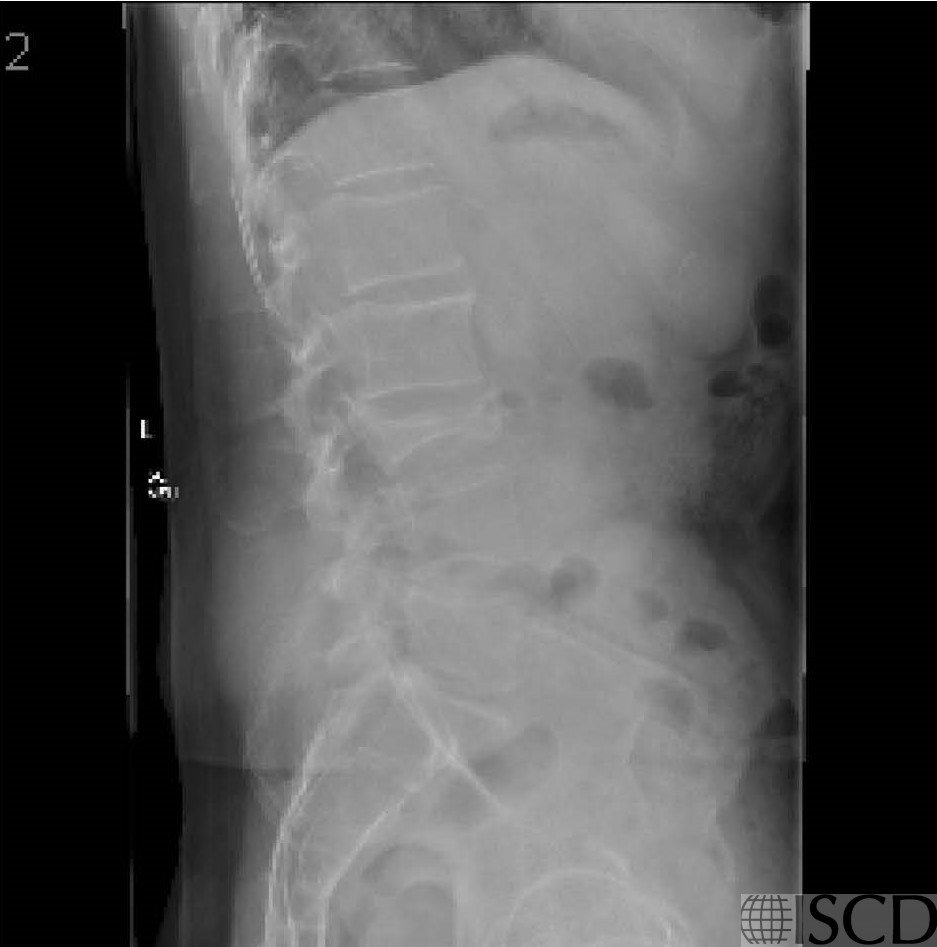

Burst Fracture of L3

This is the accompanying radiograph showing the compression fracture at L3.

The Hologic DXA scan shows a compression fracture at L3. The accompanying lateral radiograph shows a L3 compression fracture. The fracture was a burst compression fracture.